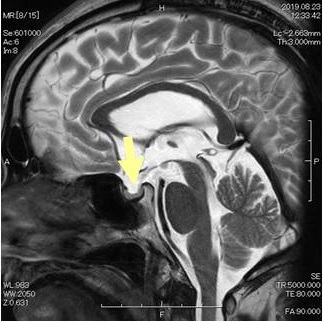

エンプティ・セラ症候群(empty sella症候群, トルコ鞍空洞症候群)は、クモ膜下腔がトルコ鞍内に下垂し、脳脊髄液で満たされた状態。原因は原発性、妊娠、自己免疫性下垂体炎、下垂体卒中、下垂体手術や放射線療法後。症状は視力障害、頭痛、脳脊髄液漏、下垂体機能低下症、中枢性甲状腺機能低下症[視床下部性(3次性)甲状腺機能低下症]、視床下部機能障害、高プロラクチン血症、先端巨大症、クッシング病、SITSH(TSH不適切分泌症候群)を引き起こす事も。原発性甲状腺機能低下症(橋本病・非橋本病)合併が多い。ダイナミックMRIで診断。治療は一般的に外科手術適応外。

エンプティ・セラ症候群(empty sella症候群, トルコ鞍空洞症候群)は、クモ膜下腔がトルコ鞍内に下垂し、トルコ鞍が脳脊髄液で満たされた状態です。

鞍隔膜の形成不全→トルコ鞍で髄液の拍動を強く受ける→くも膜下腔が下垂→下垂体が菲薄化

エンプティ・セラ症候群(トルコ鞍空洞症候群)による

- 視床下部性(3次性)甲状腺機能低下症(Endocr J. 2009;56(4):585-9.)

エンプティ・セラ症候群(トルコ鞍空洞症候群)は一般的に外科的手術の適応になりません。髄液漏では、腰椎穿刺によるドレナージ、瘻孔の修復、シャントがおこなわれます。